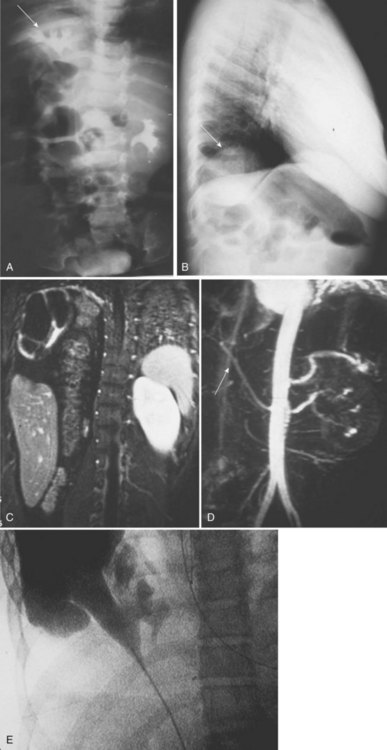

Anomalies of other organ systems are found frequently in affected individuals. The more common sites involve the cardiovascular (30%), gastrointestinal (25%), and musculoskeletal (14%) systems (Emanuel et al, 1974) (Fig. 117–6). They include septal and valvular cardiac defects, imperforate anus and anal or esophageal strictures or atresia, and vertebral or phalangeal abnormalities (Jancu et al, 1976; Wheeler and Weaver, 2001; Rai et al, 2002). Dursun and colleagues (2005) found that 44% of individuals with a congenital solitary kidney, most of whom had URA, had various nonurologic anomalies, but they detected lower incidences of these problems (cardiovascular, 15%; gastrointestinal, 9%; neurologic, 3%; and hematologic, 6%) than previously reported by Emanuel. Chow and colleagues (2005) reported a similar incidence of 42%.

Figure 117–6 Contrast CT scan showing (A) right and left orthotopic kidneys. B, Right midabdominal malrotated supernumerary kidney.

The supernumerary kidney is a distinct mass of renal parenchyma that may be either completely separate or only loosely attached to the major kidney on the ipsilateral side. In about 60% of cases, it is located caudad to the dominant kidney, which is in its orthotopic position in the renal fossa. When a separate and distinct ureter is present, the supernumerary kidney is more likely to be cranial to the dominant kidney but caudal to the adrenal (Bernik et al, 2001). Occasionally, the supernumerary kidney lies either posterior or superior to the main kidney, or it may even be a midline structure anterior to the great vessels and loosely attached to each of the other two kidneys (see Fig. 117–6). The supernumerary kidney may become wedged between the lower poles of a right and left kidney, leading to the radiographic appearance of a “pseudohorseshoe” kidney (Macpherson, 1987). A pelvic supernumerary kidney has also been reported (Eberle et al, 2002).

The ureteral interrelationships on the side of the supernumerary kidney can be variable (Kretschmer, 1929). Convergence of the ipsilateral ureters distally to form a common stem and a single ureteral orifice occurs in 50% of the cases (Exley and Hotchkiss, 1944; N’Guessan and Stephens, 1983), which suggests “a bud off of a bud” situation. Two completely independent ureters, each with its own entrance into the bladder, are seen in the other 50% of cases. The Weigert-Meyer principle (see Chapter 111) usually is followed, but in 10%, the caudal kidney has a ureter that does not follow the rule and enters the trigone below the ipsilateral ureter (Tada et al, 1981) (Fig. 117–7). Rarely, the supernumerary kidney has a completely ectopic ureter opening into the vagina or introitus (Rubin, 1948; Carlson, 1950). Individual case reports have described calyceal communications between the supernumerary and the dominant kidney, or fusion of the dominant kidney’s ureter with the pelvis of the supernumerary kidney (Kretschmer, 1929) to create a single distal ureter that then enters the bladder (Fig. 117–8). The vascular supply to the supernumerary kidney is anomalous and depends on its position in relation to the major ipsilateral kidney. Most investigators believe that the blood supply to the individual parenchymal masses should be separate to consider this a true supernumerary kidney (Kaneoya et al, 1989).